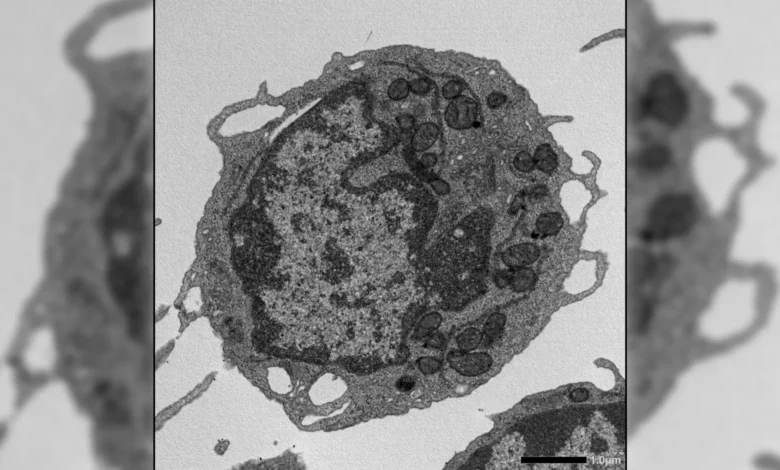

Upon activation under stress conditions, MLKL was observed to transiently translocate to the mitochondria, the powerhouses of the cell. Once at the mitochondria, MLKL instigated damage by disrupting the mitochondrial membrane potential, altering the organelle’s structural integrity, and significantly impairing its energy-generating capacity. These mitochondrial insults directly contributed to the hallmark features of HSC aging, including a diminished capacity for self-renewal, a pronounced decrease in the production of crucial lymphoid cells, and a notable skewing of output towards myeloid cell lineages. This discovery marks a significant departure from the traditional understanding of MLKL’s function, highlighting its capacity to induce functional decline without triggering cell demise.